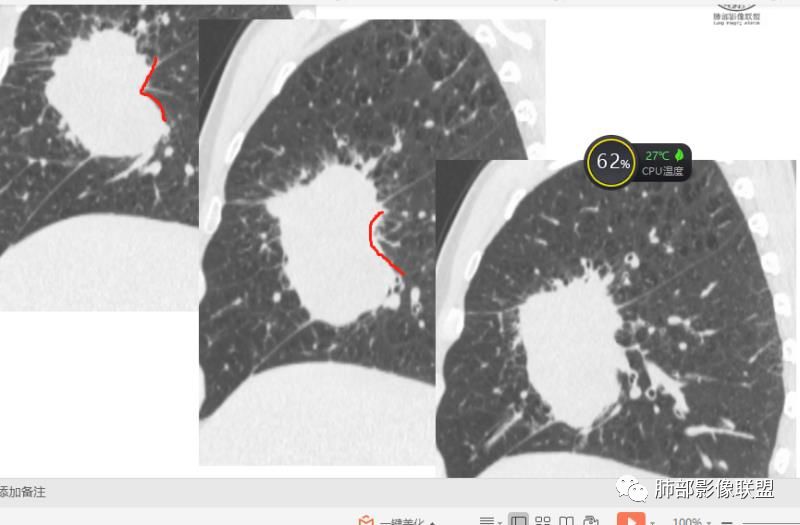

初学者:

可以看到斜裂一侧往上一侧往下,那么就是说病灶应该是起源中叶,往上,往下侵犯这样

是这样吗?

只有这个位置起源得才能做到,将叶间裂上下往不同方向推

斜裂向下推移了,水平裂向上推移了。

@吴婧南京市第一医院 这个从影像表现,坏死情况,以及叶裂推移情况与支气管推移情况来看,还是支持中叶间质来源,外朝内生长,同时向上,向下,向内都有推移作用。

下半段斜裂推移朝下

水平裂推移朝上

定在中叶应该没问题